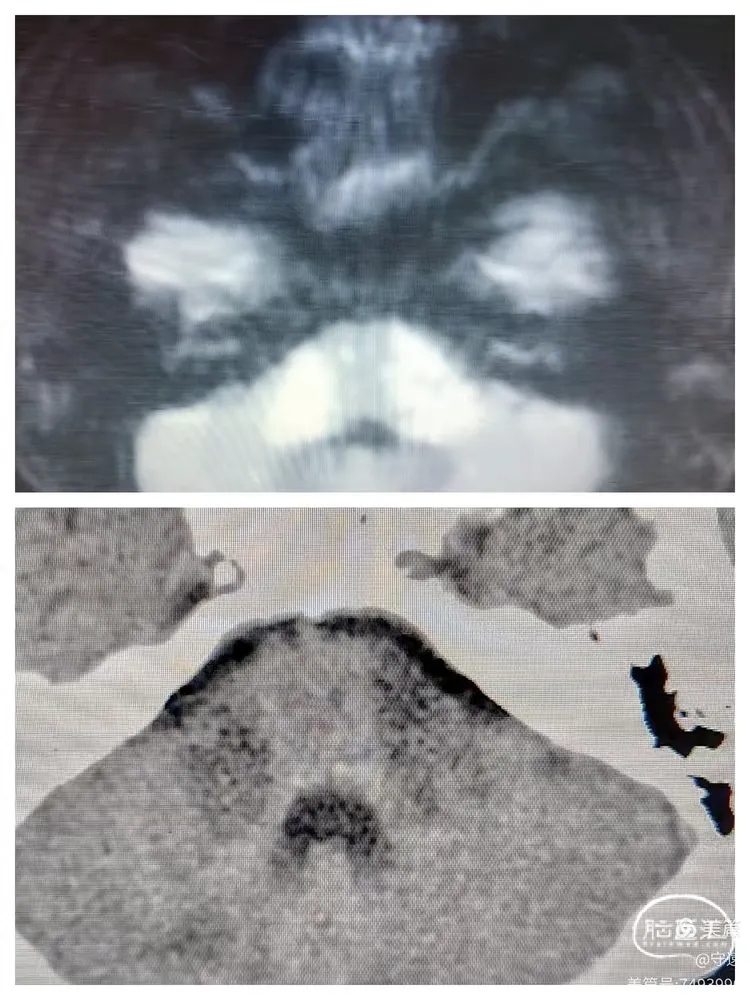

患者可按指令动作,言语障碍,左侧下肢力弱,生命体征正常。复查CT:双侧桥臂浅淡低密度影,与术前核磁大致相同,无出血征像。中脑、延髓区域未见明显梗塞。

术前核磁与术后12小时CT检查对照

2.双侧大脑脚梗死影像学犹如米老鼠两只耳朵,称之为“米老鼠耳征."